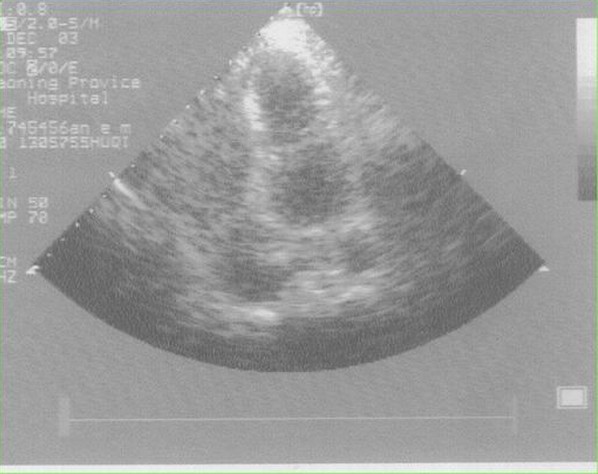

体表超声心动图:?下壁心肌梗死(下壁心肌运动减弱)。

临床所见:异常肥厚肌束或纤维肌隔将左心室分成主副两个腔。主腔通常位于基底部,与二尖瓣口和主动脉瓣口相连,副腔位于心尖部或主腔左外侧,与主腔通过一小孔或小梁间隙相通。

诊断方法:超声心动图和/或冠状动脉造